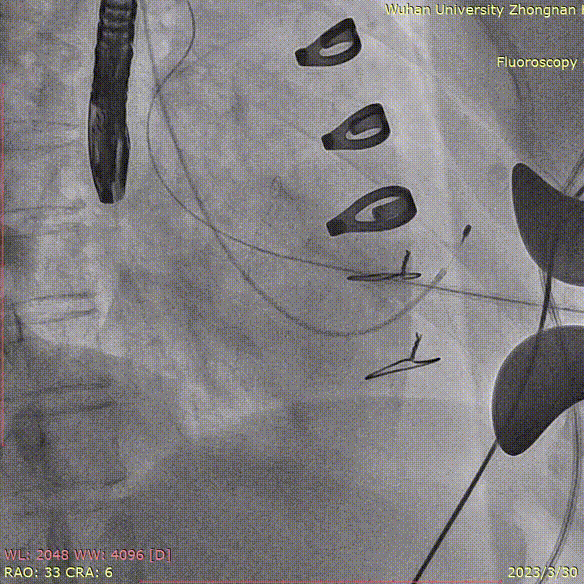

猪尾放置于无冠窦行根部造影:

定位件于瓣环下打开,将瓣膜件降至合适平面,造影确认:

定位件入窦,造影:

调整导丝,使得瓣膜同轴:

再次造影确定位置:

释放瓣膜,复查根部造影,未见明显反流,瓣膜形态和位置满意,双侧冠脉未见遮挡征象: